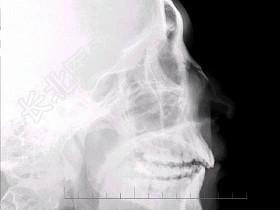

- 多项选择题男,24岁, 鼻部被击伤,如图所示, 最可能的诊断是 ( )

A、鼻骨中段见透亮线影

B、鼻骨远端稍塌陷

C、鼻骨骨折处可见小骨片影向下方分离

D、考虑为鼻骨线性骨折

E、鼻骨粉碎性骨折